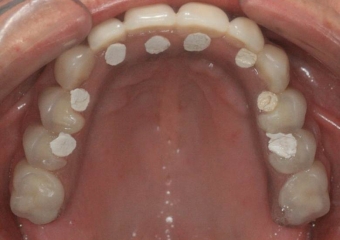

Prótese fixa em resina sobre implantes, restaurada provisoriamente